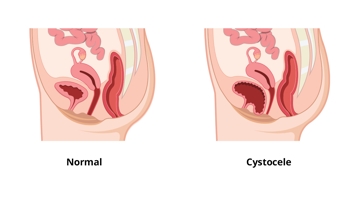

Prolaps bedeutet "aus dem Platz fallen". Ein Beckenorganprolaps (BOP) tritt auf, wenn die Scheidenwände, die Gebärmutter oder beides ihre normale Unterstützung verlieren und verrutschen. Andere nahe gelegene Beckenorgane, wie die Blase oder der Darm, können betroffen sein und ebenfalls aus ihrer normalen Position im Körper "vorfallen". Die Zystozele ist die häufigste Art von BOP.